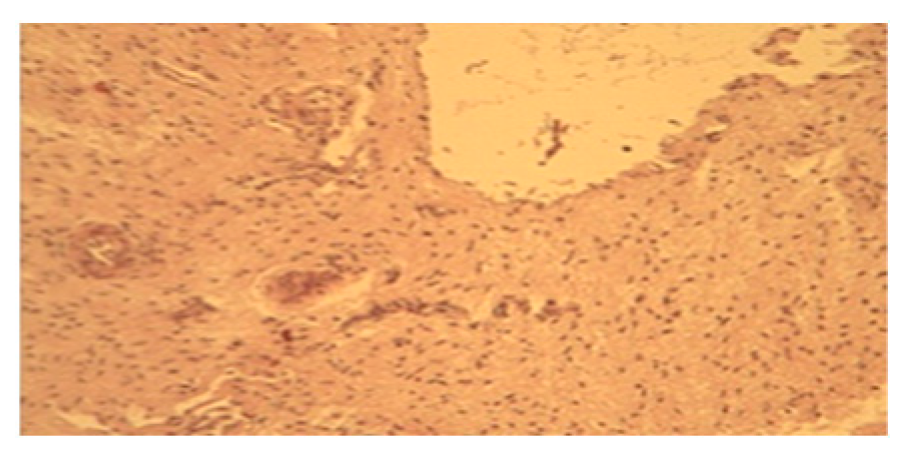

3.4. From 11th to 14th Postpartum Day

During the second week we observe: The surface epithelium is poorly regenerated and desquamated in a few places (Figure 4a). The uterine glands underwent an increase in number and size, they are circular or elongated in shape, they can be scattered in the lamina propria or organized in clusters, and they are surrounded by blood vessels (Figure 4b).

Figure 4.

(a) Histological section of the endometrium between the eleventh and fourteenth day postpartum (10). (b) Histological section of the endometrium between the eleventh and fourteenth day postpartum (40).